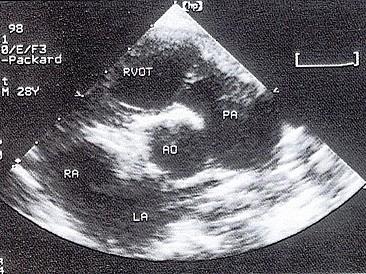

该病例最可能的诊断?(?)A.动脉导管未闭B.共同动脉干C.主肺动脉间隔缺损D.大动脉异位E.肺动脉狭窄

问题 该病例最可能的诊断?(?)

选项 A.动脉导管未闭 B.共同动脉干 C.主肺动脉间隔缺损 D.大动脉异位 E.肺动脉狭窄

答案 C